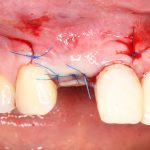

Наложение швов.

Если на этапе разреза и формирования раны всё сделано правильно, то наложение швов не вызывает особых трудностей. Периостотомия или послабляющие разрезы на периосте не требуются (ни практически никогда не требуются). А сами швы получаются аккуратными и герметичными:

Обрати внимание, что все шовные лигатуры находятся в пределах кератинизированной десны. Это позволяет избежать деформации тканей и лишних рубцов. В наиболее уязвимых местах (около зубов) шовные лигатуры лучше продублировать.

Если бы мне пришлось делать это сейчас, то я бы использовал непрерывный «матрацный» шов. Он удобнее, быстрее в наложении и комфортнее для пациента. Минус — если распускается, то распускается весь. К тому же, его очень неудобно снимать.

Несмотря на то, что уже тогда мы широко использовали непрерывные швы в подобных случаях, здесь я, во-первых, зассал (может распуститься), во-вторых, снятие швов предполагалось в поликлинике по месту жительства пациентки, и мне не хотелось, чтобы там при снятии швов начудили. Как выяснится позже — зря беспокоился.

Неизменно одно — в таких операциях мы использовали и до сих пор используем нерезорбируемые монофиламентные шовные материалы, поскольку они наиболее гигиеничные. Чтобы острые концы нитей не беспокоили пациента, их можно оплавить нагретой гладилкой или гуттаперчевым плаггером.